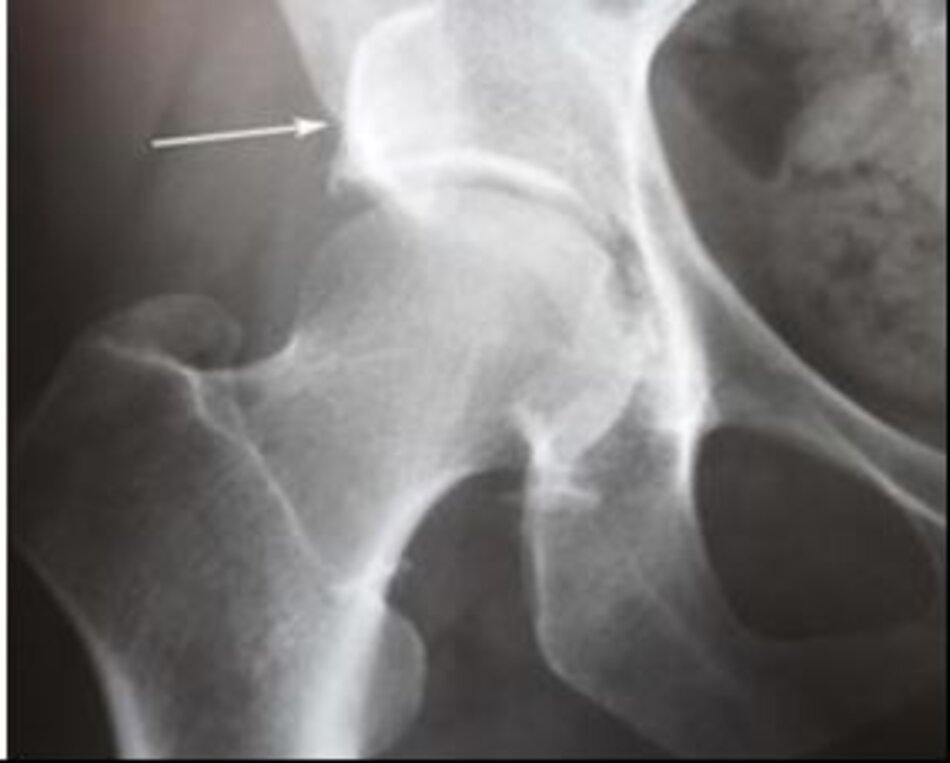

Xquang trước mổHình ảnh hoại tử chỏm xương đùi trái

Xquang trước mổ. Hình ảnh hoại tử chỏm xương đùi trái